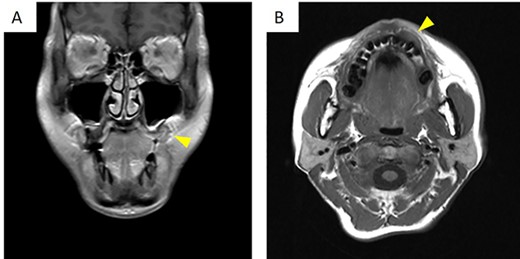

There was no evidence of bony swelling or resorption on computed tomography (data not shown). On magnetic resonance imaging, contrast-enhanced T1-weighted images showed a mass with low signal (Fig. 2A and B), measuring 19.3 × 12.1 × 9.2 (length × breadth × thickness) mm. It showed thickening of the mucosa at the left upper gingival cheek transition. The mass did not infiltrate the alveolar bone and had a relatively clear border with the surrounding area.

On magnetic resonance imaging, contrast-enhanced T1-weighted images showed a row signal. (A) Frontal cross-section. (B) Horizontal cross-section. The arrowheads indicate the tumor.